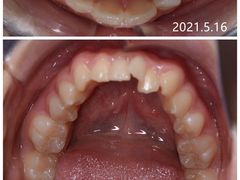

番茄宝妈 | 22-10-23

报错

• -新达口腔(华东理工大学店)